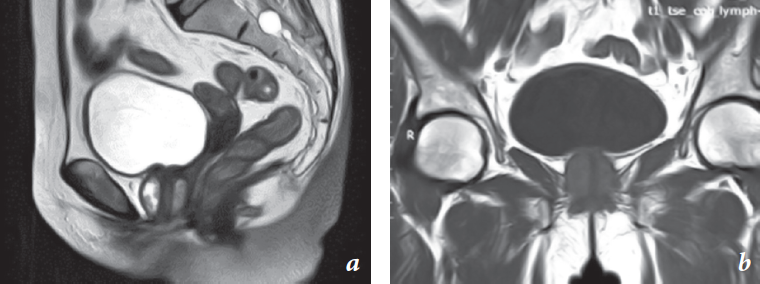

Patient V., 56 years old, visited an urologist with complaints on frequent urination, discomfort, and recurrent bloody-purulent discharge from the urethra. She was consulted by a gynecologist and based on the results of the transvaginal ultrasound and bimanual examination, with a diagnosis of paraurethral cyst and suppuration on October 22, 2018, she was hospitalized at the urology department. According to the results of bladder ultrasound examination (10/26/18), a rounded hypoechoic formation with uneven blurred contours was revealed in the projection of the urinary bladder neck, with heterogeneous echostructures up to 30 × 26 mm in size. With color Doppler mapping, peripheral blood flow was located in the urinary bladder after micturition, and the volume of residual urine was 87.6 ml. Chest fluoroscopic image done on October 22, 2018 revealed no pathology. The concomitant pathology was a small uterine myoma. According to the ultrasound examination, the organs of the abdominal cavity and kidneys were normal. On October 29, 2018, in the operating room, when an attempt to isolate a paraurethral formation (cyst) from the tissues of the anterior vaginal wall through the external opening of the urethra was made, a hemorrhagic discharge with tissue detritus occurred. Cystourethroscopy was performed and it revealed the clean and pink mucous membrane of the bladder, and the slit-like orifices in a typical place. In the area of the urinary bladder neck, the mucous membrane was edematous and dull. When examining the urethra, pronounced venous congestion was noted, and in the middle third at the 7 o’clock position, an ulceration/defect of up to 3 mm was found, which was a source of scanty bleeding, and no tumor tissue was revealed. A biopsy of the flat zone of the mucous membrane was performed from the region of the bladder neck using a 24 Ch resectoscope. Tissue detritus from the urethra was sent for cytological and histological examination. On October 30, 2018, magnetic resonance imaging (MRI) of the pelvic organs was performed, which showed a 1.5–2 cm thick densely elastic tissue growing visually in the projection of the urethra (Fig. 1).

Fig. 1. MRI images of the pelvic organs of patient V., 56 y. o.: a – frontal projection, b – sagittal projection. A tumor with a clear outline is located around the urethra

Рис. 1. Магнитно-резонансная томография органов малого таза пациентки В., 56 лет: a — фронтальная проекция, b — сагиттальная проекция. Опухоль с четкими очертаниями расположена вокруг уретры